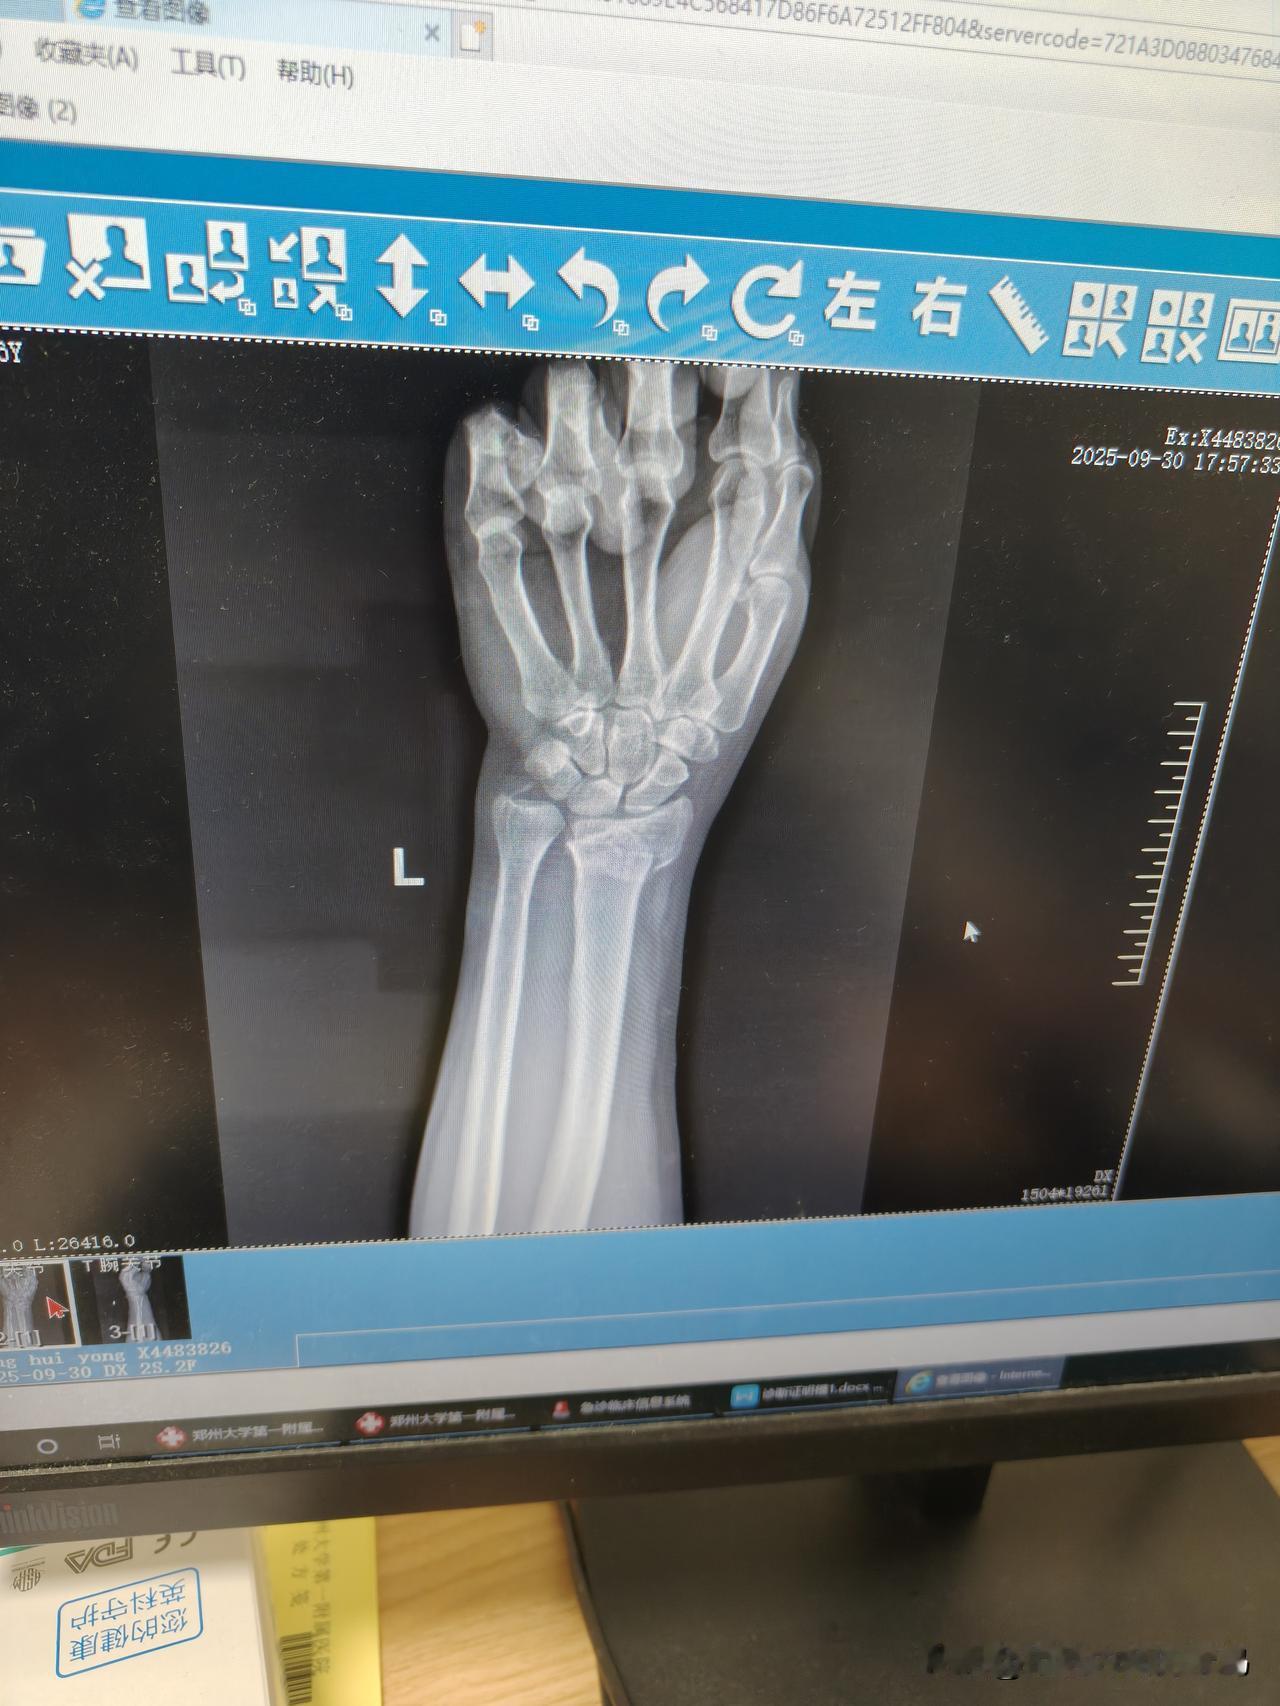

到底西医刀到病除,还是中医妙手回春? 霉气都是自找的! 节前最后一天,大晴天,已经连续下了大半个月的雨,从10月1日开始再下半个月,气温直接干到个位数。所以想抓住为数不多的晴天,晒晒太阳,修复心情。 沿着河边走路,沐浴着阳光,欣赏着秋景,一切都是那样的自然。 好奇害死猫。男人对钓鱼根本无免疫力,看到桥下有钓友中鱼,兴冲冲跑过去,忽略了半坡的湿泥,直接一滑,左手本能撑地。 悲剧来了,钻心的疼,两鬓豆大的汗珠,在朋友的帮助下坐在旁边缓缓,止不住的疼,还有湿透的后背。朋友拉着我去医院拍片检查,看看有没有骨折。 还好最近的医院就是宇宙第一大医院的东院区,挂了急诊去拍片。内心希望是挫伤,最坏的是骨折,现实生活中往往就是最坏的结果,确认骨折!附图一。 急诊医生把片子发给主治医生等治疗方案,等了一会主治医生过来了,直接说必须住院手术!先消除瘀血肿胀,等几天手术打入钢钉!整个假期全完了! 问问能否正骨复位,得到的是西医只会手术,不会正骨。没办法,我把结果拍下来发给一个中医老兄,询问这种情况是不是必须要手术。 否极泰来,峰回路转。得到老兄可以正骨复位的治疗方案,心情好了很多。赶去老兄给联系的郑州骨科医院,节前的堵车很疯狂,10多公里的高架桥硬是走了一个半小时。 到了骨科医院 检查确认就安排复位操作,两个医生一人一个方向,拉扯,按摩,摔倒的时候有多疼,复位的时候有多痛,能量守恒定律。 又去拍片看复位的结果,对位对线比较理想,不用手术,得到了最满意的结果,图片二。 夹板固定,打上石膏,拿了点促进骨骼生长的药,回家静养,等候复查。 疼的睡不着,自己变成了《无间道1》中梁朝伟扮演的陈永仁,学着他发摩斯密码,苦中作乐吧。 思考一个问题,到底西医刀到病除,还是中医妙手回春? 为什么对西医的治疗方案天然排斥? 为什么对中医保守治疗更为倾向? 欢迎大家在评论区发表自己的意见。